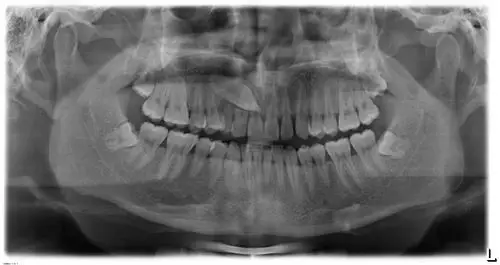

牙科ct有助于完全埋伏牙拔除术

怀疑牙龈萎缩

解决一下这种情况牙的问题 有ct片

术前ct

拍牙片出来后,有一个好大的牙长在牙龈里.

牙齿ct怎么看全景? - 知乎